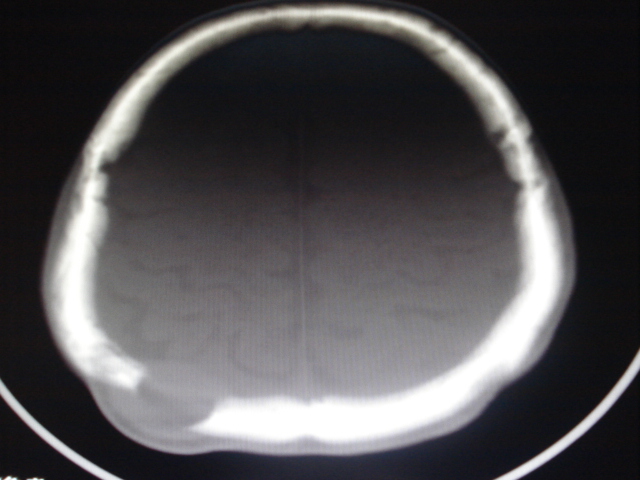

男性,48岁。发现右顶部包块一月余,质软有轻压痛。

其余没问题的层面我没有发上来,请教各位老师,可以考虑嗜酸性肉芽肿吗?

年龄大,无“纽扣样”死骨,软组织肿块密度较低且边界清楚,由内板向外破坏,不支持嗜酸性肉芽肿。

考虑转移瘤、表皮样囊肿、骨纤、板障型脑膜瘤、颅骨淋巴瘤鉴别。

倾向于板障型脑膜瘤,淋巴瘤待排除,建议增强及mri进一步检查。